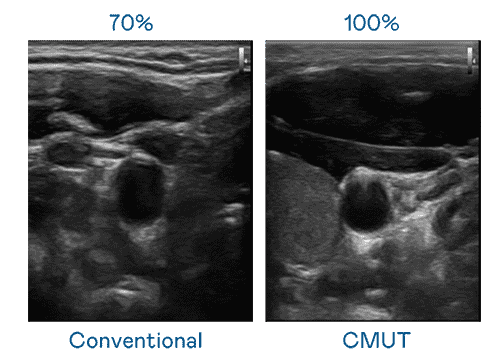

CMUT 技术是一种用电容式微机电元件来产生超音波讯号的技术。。。与传统 PZT 压电式技术相比,,,,CMUT 频宽增加 30%,,更宽频的超音波讯号让影像解析度大幅提升,,,,是实现高影像品质医疗超音波扫描、、、、促进精准医疗发展的关键技术。。。。

大频宽带来超清晰影像

超音波影像的解析度高低,,首先取决于探头能发出的讯号频宽。。OBPay CMUT 可提供高清晰的超音波讯号,,提供高频宽、、、、高灵敏度、、影像纹理细节更高的超音波影像,,,,协助医护人员缩短影像判读时间及利用精准的医疗影像进行诊断。。。